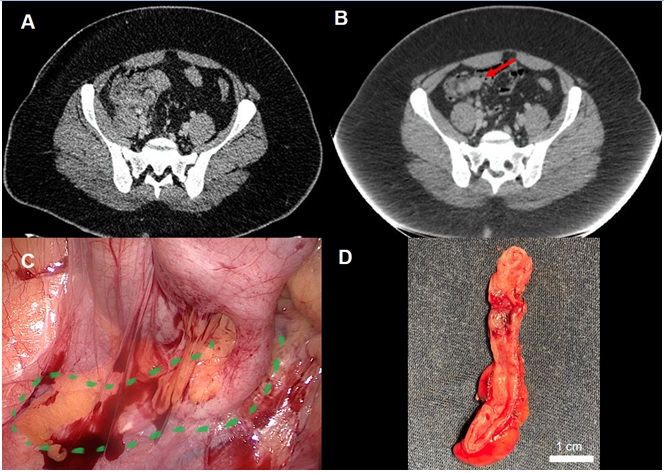

Paciente de 30 años, masculino, obeso, que ingresa a emergencia por dolor en fosa ilíaca derecha (FID) y fiebre de 10 días de evolución. Presentaba una consulta previa en policlínica a las 72 horas del inicio del cuadro donde con planteo de infección urinaria se habían indicado ciprofloxacina vía oral. Al examen físico presentaba un abdomen globuloso y una tumoración palpable dolorosa en FID. De la paraclínica se destacó leucocitosis (17.000×109/L). La tomografía computada (TC) evidenció una masa inflamatoria en FID de epicentro el complejo ceco apendicular, de paredes mal delimitadas con aumento de la densidad de la grasa adyacente de aspecto inflamatorio. No se evidenció liquido libre o neumoperitoneo (Figura 1). No se identificó el apéndice cecal.

Figura 2: Fuente: A: TC corte axial que evidencia al re ingreso proceso inflamatorio a nivel del FID, no se identifica apéndice cecal. B: TC de control a los 4 meses. Se evidencia la persistencia de imagen patológica (flecha roja). C: Intraoperatorio, apéndice cecal (en verde) D: Pieza abierta por borde anti mesentérico. Mucosa macroscópicamente sana elaboración propia.